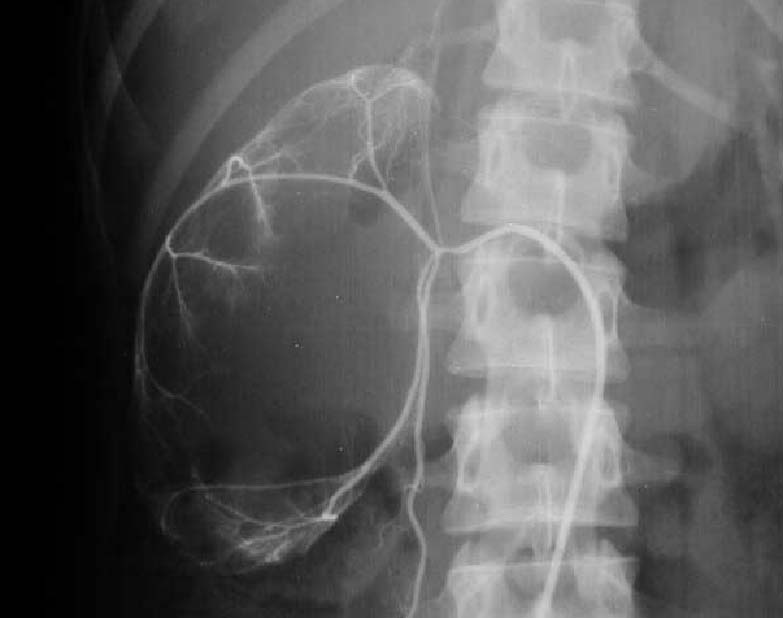

SIGNO DEL BORDE o SIGNO DEL ANILLO HIDRONEFRÓTICO

borde uro2

Fase vascular precoz del mismo estudio en el que puede verse el arqueamiento de las ramas arteriales como consecuencia de la hidronefrosis.